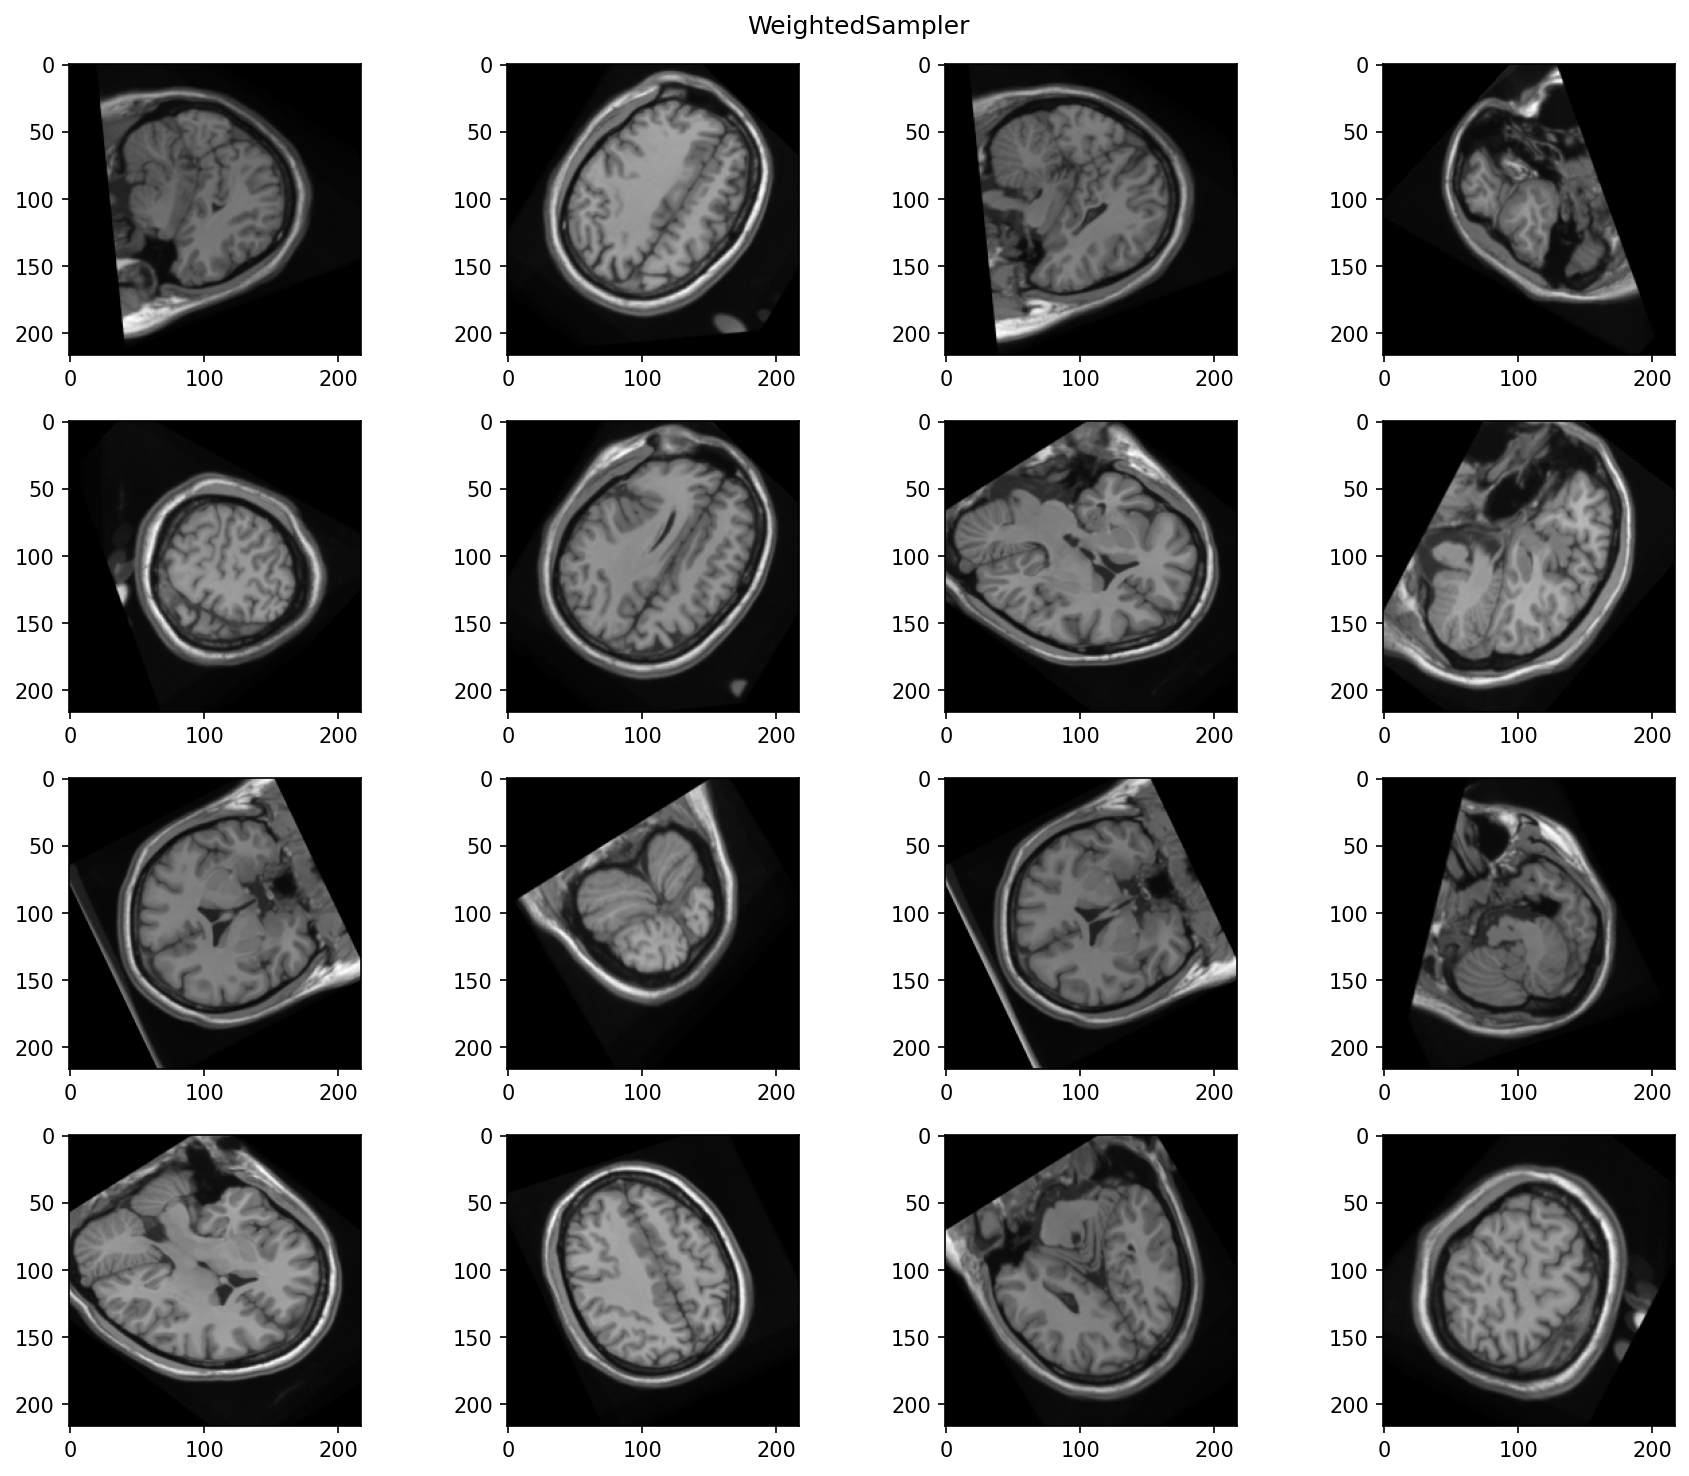

Weighted sampler

We can use the brain image contained in the subject as a probability map

for a torchio.WeightedSampler. That way, we ensure that the center

of all patches correspond to brain tissue.